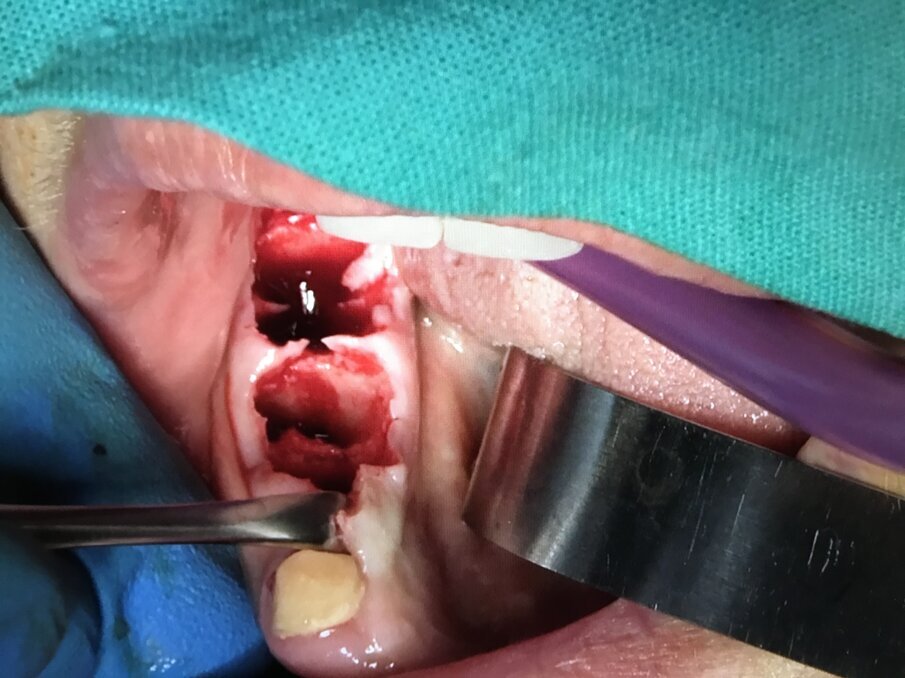

Fig. 11 - Fase 1: siti estrattivi preparati in modo traumatico con Courretage.

Fig. 12 - Fase 2: Impianti Multysystem inseriti e filino della discrepanza alveolo-implantare con I-PRF addizionato di xenoinnesto.

Fig. 13 - Fase 3: A-PRF utilizzato come membrana di contenimento. Non è necessario elevare lembi vestibolari e linguali per accollare i margini gengivali.